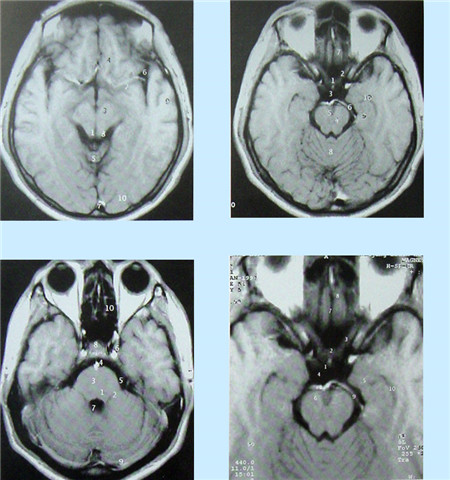

核磁共振成像無電離,對機體沒有不良影響。MRI對檢測腦內血腫、腦外血腫、腦腫瘤、顱內動脈瘤、動靜脈血管畸形、腦缺血、椎管內腫瘤、脊髓空洞癥和脊髓積水等顱腦常見疾病很有效。

超聲經顱多普勒血流分析儀(TCD)提供的是實時動態的腦血管的血流動力學資料。核磁共振血管成像(MRI)提供的是大腦實質細胞的損壞與形態學上改變的影像學資料 。數字減影血管造影(DSA)提供的是腦血管瞬間形態學上的變化,且有創傷。

數字減影血管造影DSA腦血管圖像顯示                                                      核磁共振MRI掃描腦組織圖像